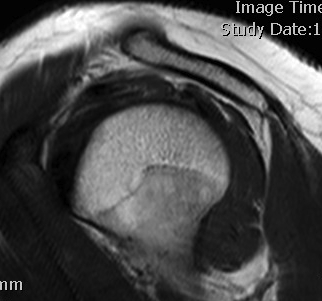

MRI

Inflammation and thickening of the rotator cuff tendons

Mild inflammation of the supraspinatus tendon insertion

Thickening and edema of the supraspinatus and infraspinatus tendon

Subscapularis tendinosis